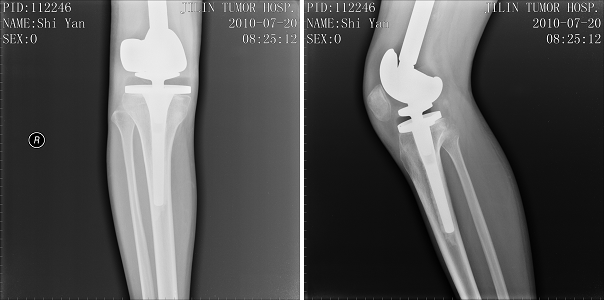

右侧股骨下端骨肿瘤,行右股骨下端骨肉瘤瘤段切除、人工假体置换术。现右膝关节可屈曲至90度,行走自如。